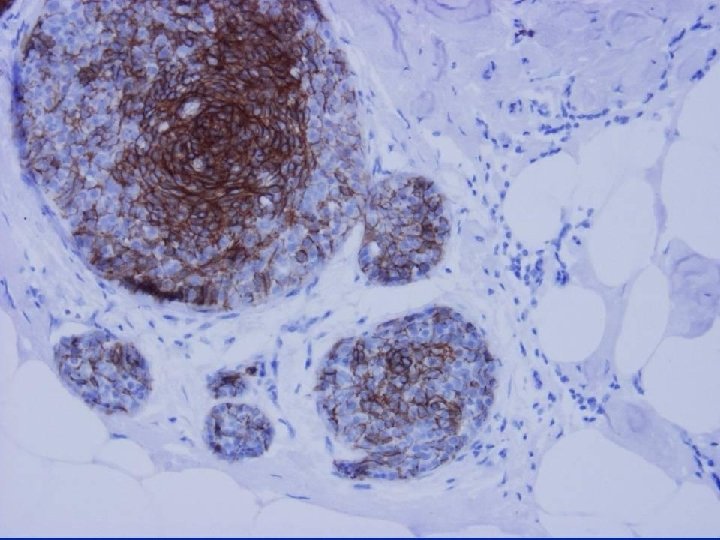

Cytokeratins in Intraductal Hyperplasia Luminal epithelial cytokeratins (CK 8, 19) & basal intermediate epithelial cytokeratins (CK 5, 6, 14) may be helpful in difficult intraductal proliferations - identify a mixed cell population in UEH Bocker W. Pathologe 1997; 18: 3 -18

Columnar Cell Lesions • Cells of columnar cell lesions show luminal • • cytokeratin (e. g. CK 19) positivity No expression with cytokeratins 5 or 14 Strong homogeneous nuclear oestrogen & progesterone receptor & bcl-2 positivity IHC not helpful in distinguishing FEA from CCC or CCH May be helpful if apocrine change or microcysts are differential diagnoses